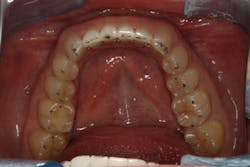

We digitally analyze our esthetics and smile design using the Dawson Diagnostic Wizard (the Dawson Academy). One of our biggest esthetic concerns in this case was caused by a functional issue. As you can see in the photos (figures 1 and 2), the patient has significantly more attritional wear on the right side versus the left. Due to the wear, the right anterior teeth have suffered from more compensatory eruption than the left, which results in uneven gingival architecture and esthetically displeasing length-to-width ratios of the anterior teeth (figures 3 and 4).

When we start to look at our occlusal shots (figures 5 and 6), it is obvious that we have some acidic erosion into dentin as well as significant wear facets from attrition. The pulp chambers of teeth Nos. 8 and 9 are now visible due to the loss of lingual tooth structure.